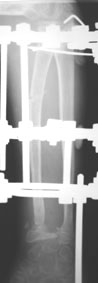

11-летний любитель лазить по деревьям 7 месяцев назад получил открытый дистальный остеоэпифизеолиз левого луча. ПХО была сделана с трудом; о репозиции, со слов, и не помышляли. Неделю назад удалось открыто адаптировать костные фрагменты, фиксировать аппаратом. Сразу сделали кортикотомию в/3 луча. Начали его удлинение. Вопрос: учитывая отсутствие дистальной зоны роста стоит ли "переудлинить" луч? Если да, то на какую величину?

Глядя на предложенные снимки, сразу же возникает вопрос о необходимости открытого сопоставления отломков лучевой кости. Мне кажется, репозицию возможно было бы сделать и ваппарате Илизарова с использованием смещенных шарниров и этапной дистракции без выполнения разреза. Росковый хрящ, скорее всего, большей частью погиб. Но в аппарате Вы могли срепонировать и стабилизировать отломки, восстановить на время соотношение лучевой и локтевой костей в лучезапястном суставе, пусть даже дозированной осевой дистракцией.

Маленькое замечание: кортикотомия произведена (кажется так по снимку) в невыгодном с точки зрения кровоснабжения кости месте. Дитракция в аппарате приведет к сдавлению не растянутого в аппарате лучезапястного и межзапястного суставов (спица за пястные кости не проведена).

Проведена. Иначе как бы фрагменты удерживались? Через дистальный фрагмент луча спицу предполагаю провести в конце периода дистракции. Если пациента за праздники не увезут обратно в Херсон - есть и такая вероятность. Еще раз благодарю всех.